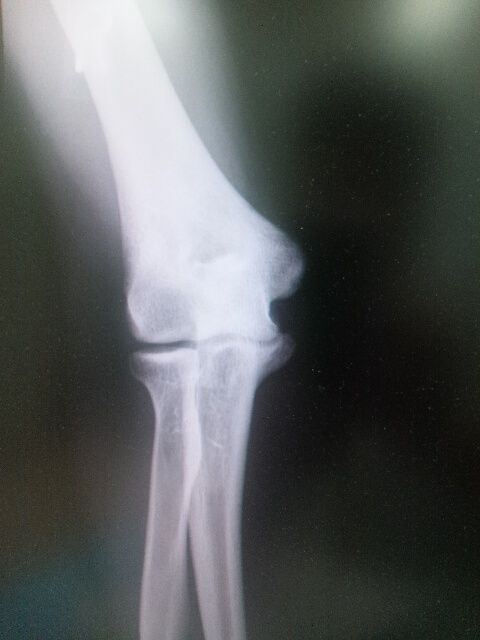

チーム MINOSIMA の右投手の治療の依頼です。

右肘を痛め 急遽 西武ドームから 当院にて  治療開始しました、

筋肉をゆるめた後、注射とテーピングで痛みは消失し

昼からの決勝に望みました

結果 全国優勝を果たしました!